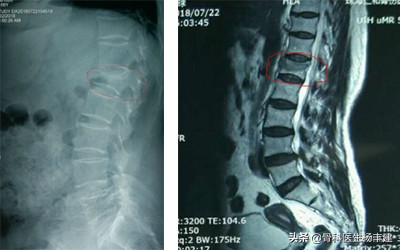

左侧X光可见红圈中的椎体明显变扁了,核磁共振可以看到颜色不一样,说明是新鲜骨折

这时候就需要核磁共振出手了。核磁共振检查可以分辨这些变形的椎体中,哪一个是新的骨折,哪一个是老的骨折或者压根不是骨折。有一些老人有金属的心脏支架或者其他的问题,不能做核磁共振,则使用CT代替,CT通过分析骨小梁是否压缩,骨皮质是否断裂也可以进行甄别,只是没有核磁共振更清楚和准确。

对于皮质变形明显的骨折,CT重建的图像也很清楚,红箭处为两个椎体骨折